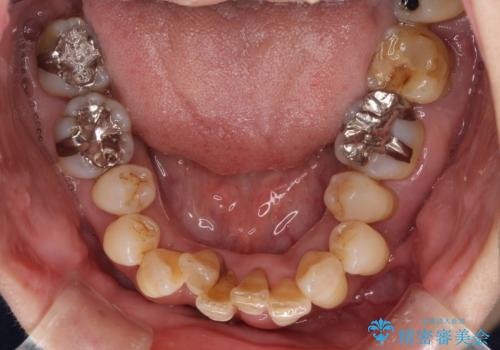

診察を行ったところ、重度歯周病の状態の上に上下の歯列が著しい叢生という状態でした。

歯周初期治療として抜歯や歯槽骨再生治療を行い、さらに歯周ポケット除去を行った後に矯正治療で歯列を整えて行くこととしました。

2~3年は早く終了する予定でしたが、途中で体調を崩されて来院されない時期が続いたため、非常に長期間の治療となりました。